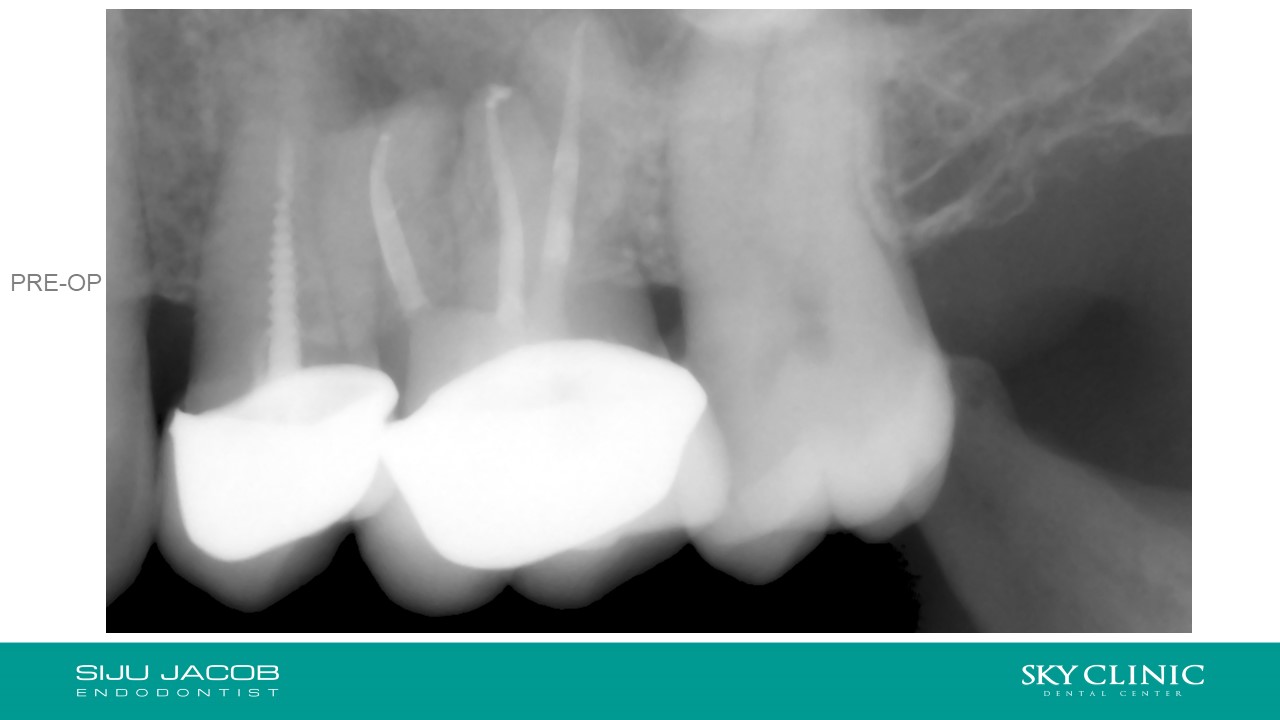

Selective Re-treat of Missed MB2